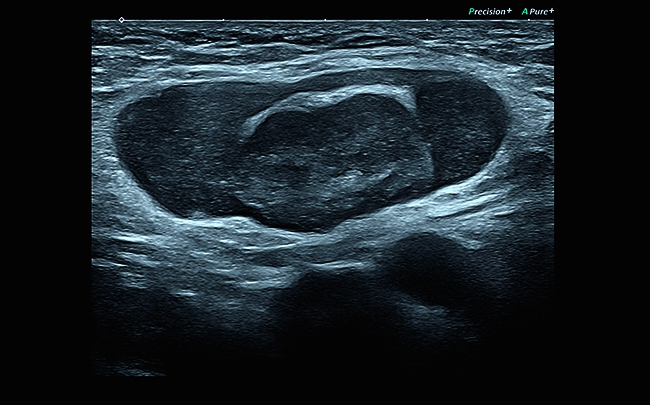

Компрессионная эластография

Эта методика выявления опухоли, построенная на анализе отличий модулей продольной упругости, была принята в качестве общего стандарта и применяется для детального исследования поверхностно расположенных органов. С ее помощью вы сможете добиться детального и по-настоящему качественного результата проводимого исследования.

Эластография:

Компрессионная, Сдвиговая

Эластография сдвиговой волной/Эластометрия:

Да

Компрессионная эластография: